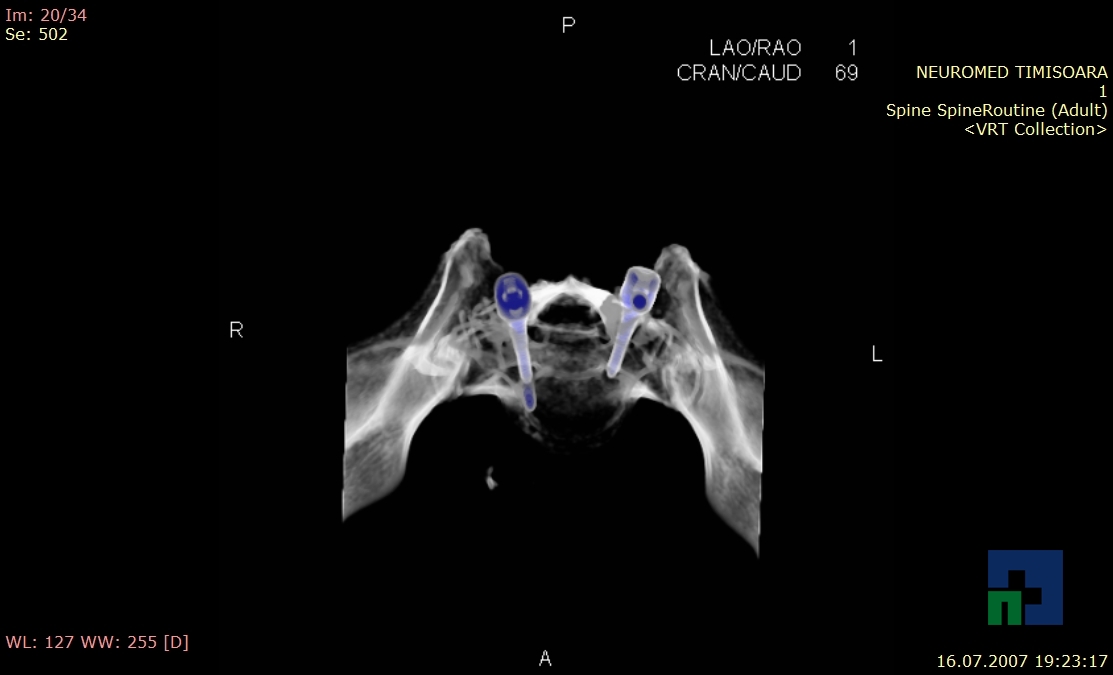

- Diagnosticul fracturilor:

- Unice

- Multiple

- Cu înfundare

- Complexe cranio-sinusale

- Complexe cranio-etmoidale

- Complexe cranio-orbitare

- Complexe cranio-faciale